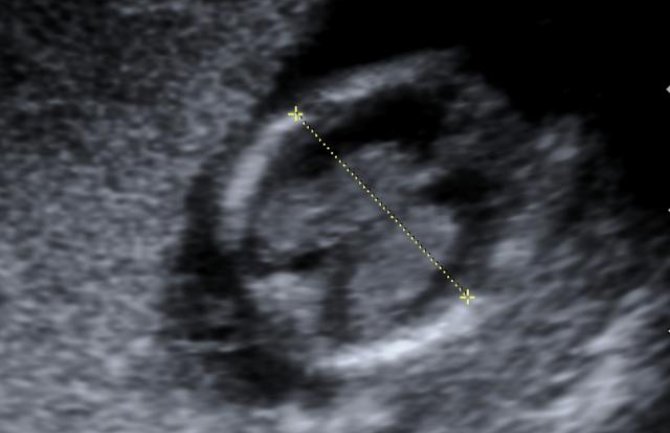

Kod njega je na posljetku dijagnostikovano stanje „foetus in fetu“ do kog dolazi u ranim fazama blizanačke trudnoće, kada jedan fetus ulazi u drugi putem pupčane vrpce. On tu postaje parazit živjeći od tijela svog brata ili sestre.

U Kumarovom slučaju, fetus je u tehničkom smislu bio živ i rastao je zbog metaboličkih aktivnosti u njegovom tijelu.